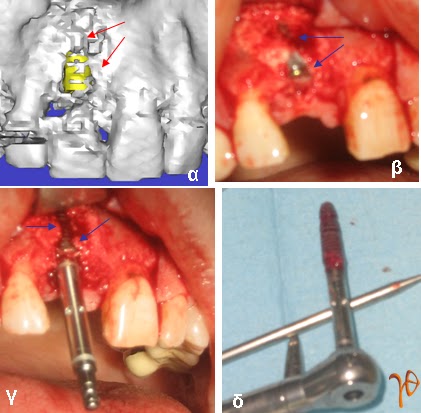

Περίπτωση 1: Αντικατάσταση οδοντικού εμφυτεύματος στη θέση #11

Εικόνα 1.1: (α) τρισδιάστατη απεικόνιση τοποθετημένου εμφυτεύματος #11 με φτωχό αισθητικό αποτέλεσμα και σημεία φλεγμονής με οστεολυσία (βέλη), (β) διεγχειρητική εικόνα εμφυτεύματος (βέλη), (γ) και (δ) αφαίρεση εμφυτεύματος (βέλη)